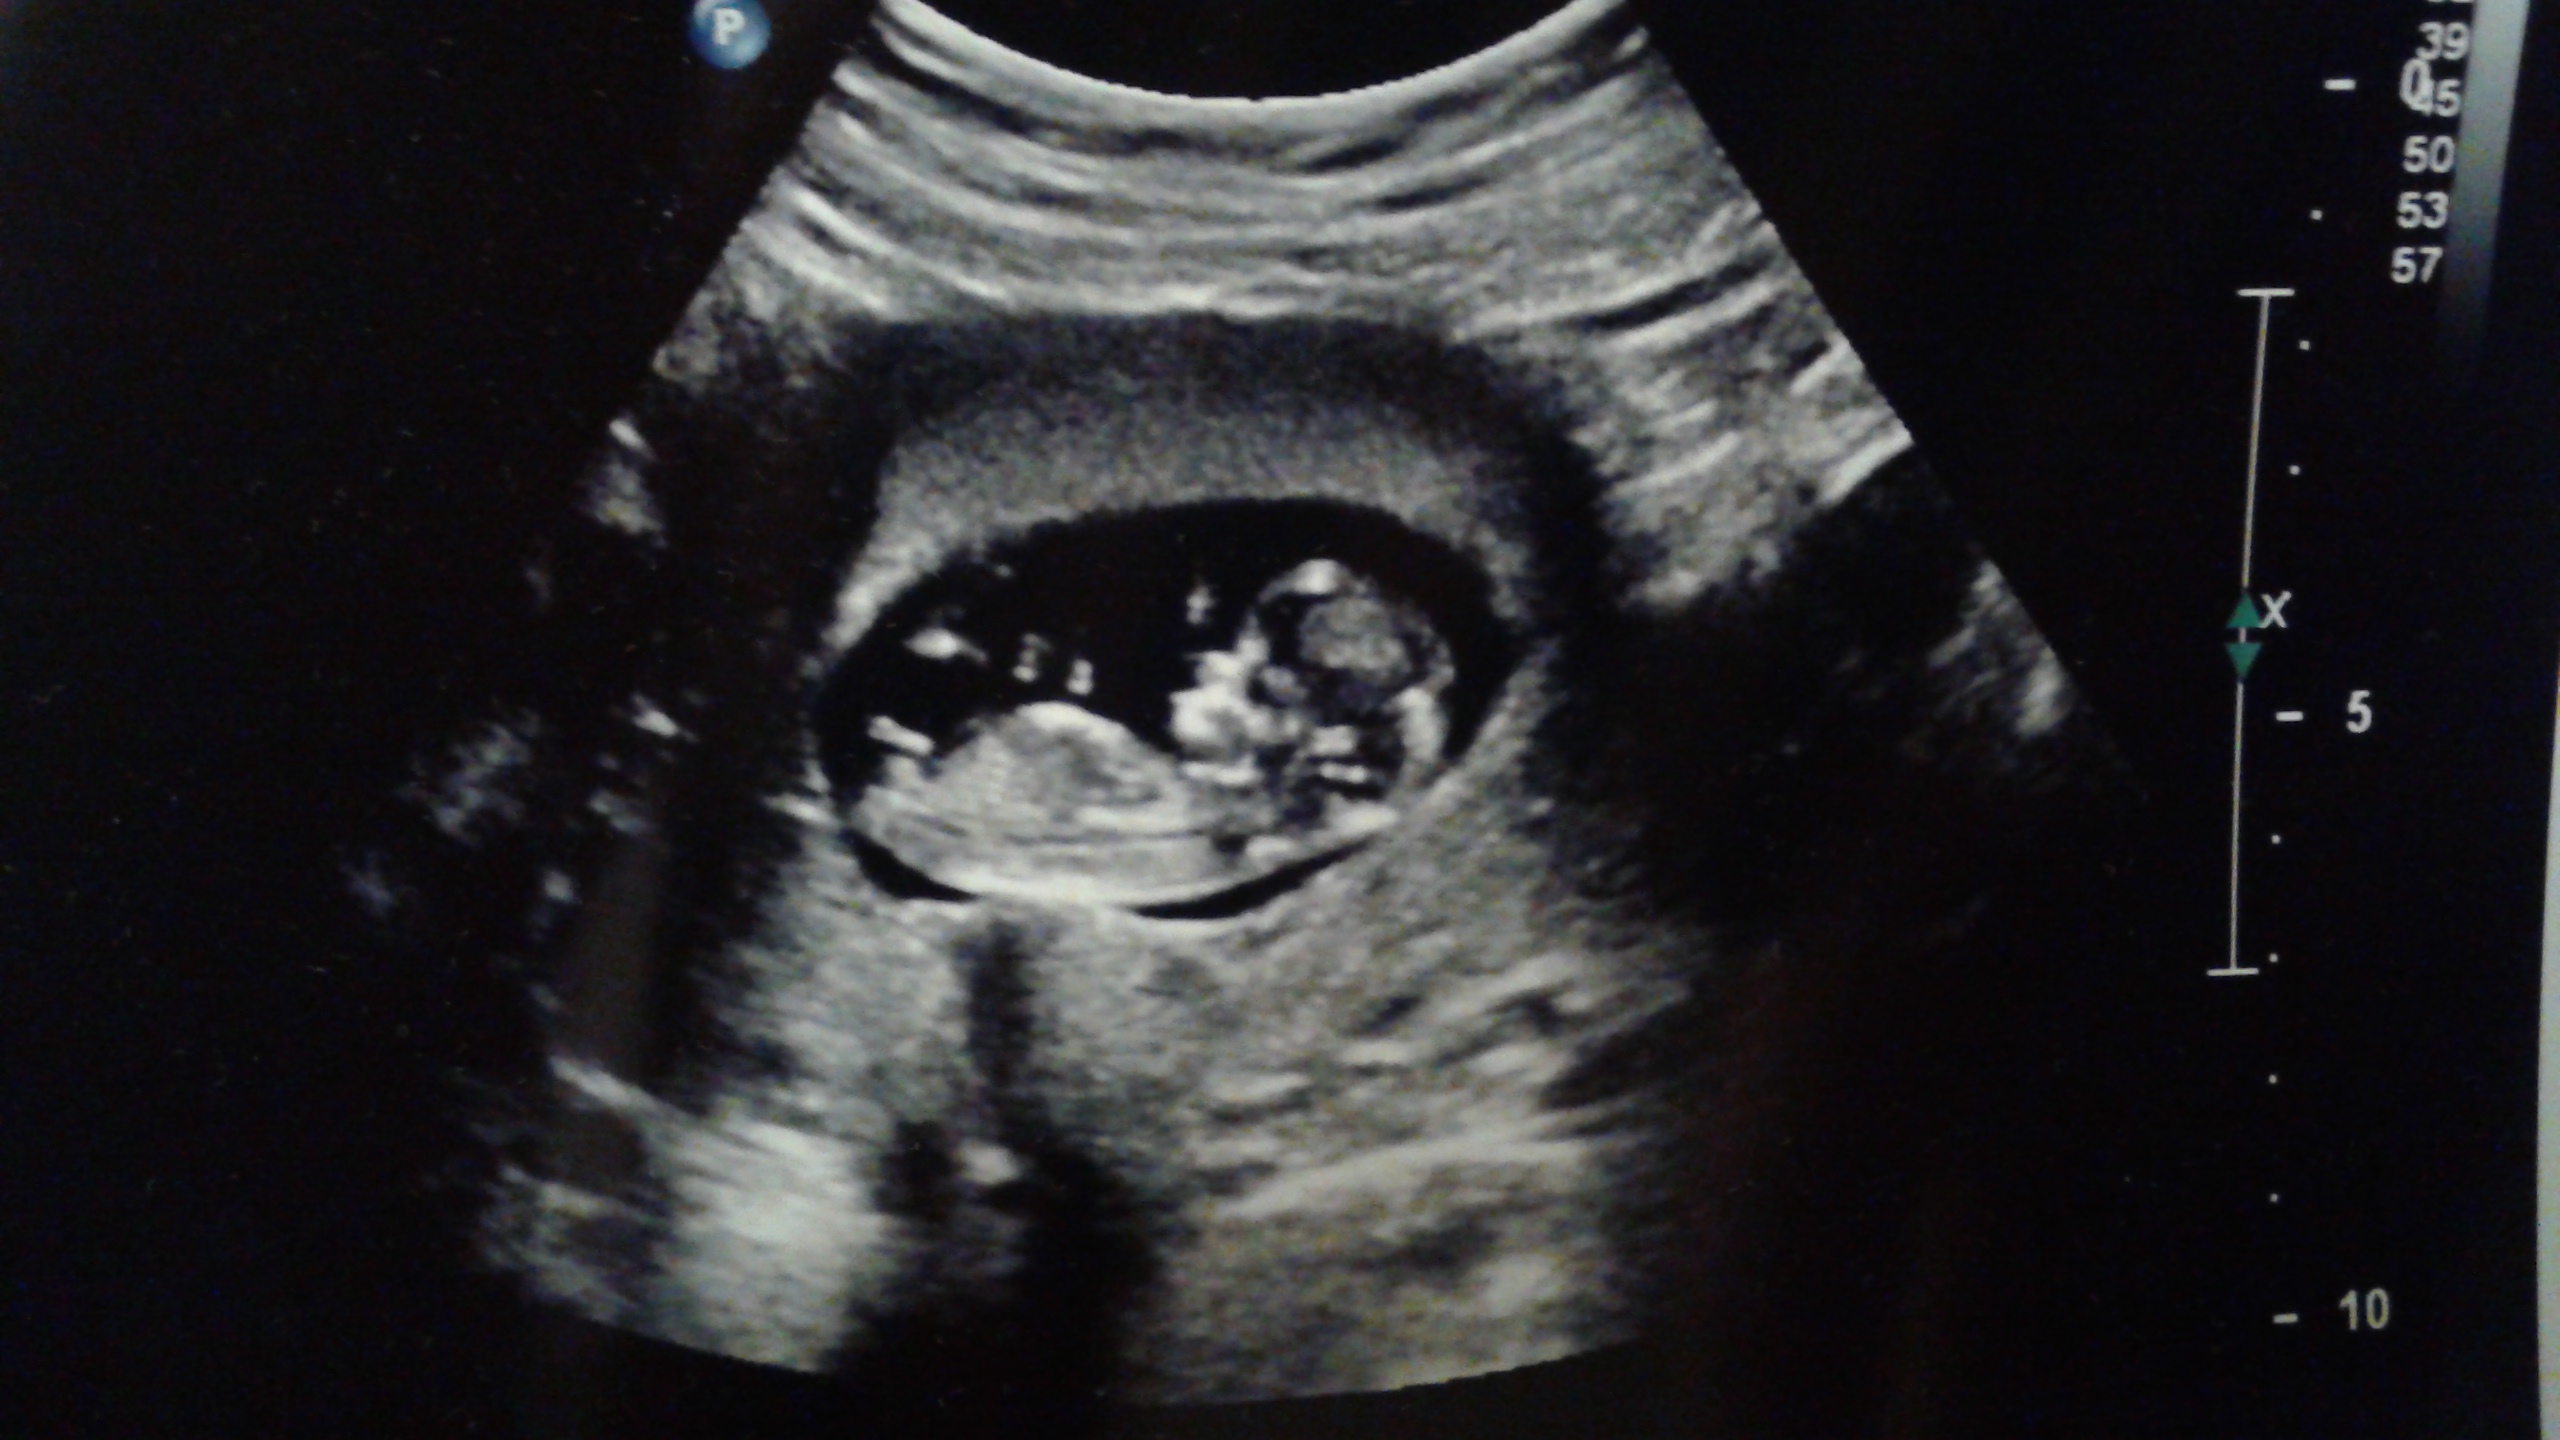

So i'm in that grey area where it's too late for Ramzi's method, but too early for Nub or Skull theory. I'm at 11w5d in the ultrasound. Just posting this picture for guesses, I know it's not accurate this early. I will be finding out the results of my genetic testing in 2 weeks (from today... the 24th) so I will know for sure then.

Attachment 23845